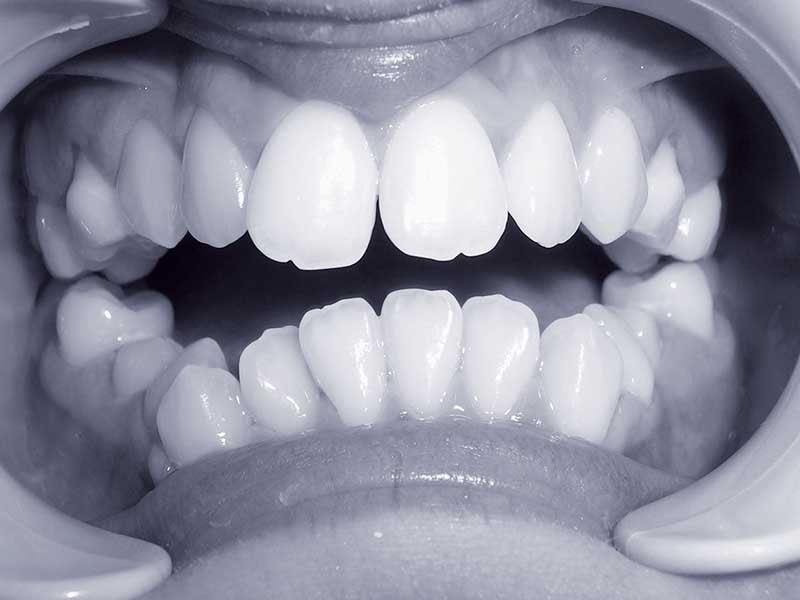

Pour les raisons précitées, les traitements orthodontiques menés en collaboration avec un chirurgien maxillo-facial sont de plus en plus fréquents [7]. Dans le cas clinique qui illustre cet article, il s’agit d’une jeune fille âgée de 13 ans lors la première consultation (fig. 1, 2, 3).

Sur le plan squelettique, elle présente une classe 3 par rétromaxillie dans un profil cisfrontal associé à une hyperdivergence faciale. La proalvéolie incisive maxillaire et la forte rétroalvéolie incisive mandibulaire singularisent le secteur alvéolo-dentaire (fig. 4 et 5).